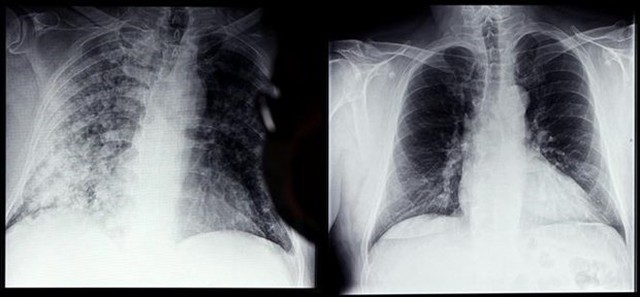

/https://cms-prod.s3-sgn09.fptcloud.com/nhung_dieu_ban_can_biet_ve_xo_phoi_sau_covid_v_Iv_BO_1661263521_129bf9f7da.jpg)

Một trong những mối đe dọa với các bệnh nhân hậu Covid chính là tình trạng xơ phổi. Xơ phổi hậu Covid có thể ảnh hưởng rất lớn đến sức khỏe người bệnh nếu không được phát hiện và điều trị kịp thời.